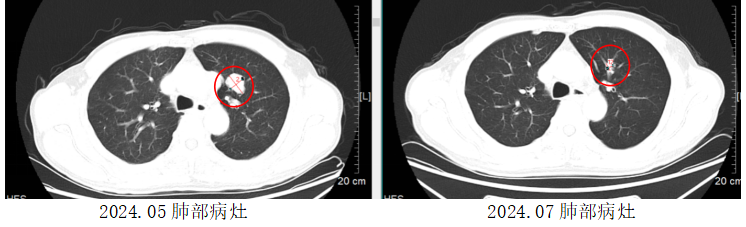

另一位患者,58岁的孙先生(化名)被诊断出胰腺神经内分泌癌伴双肺、腹腔、锁骨区、纵膈淋巴结转移。他慕名至我院肝胆胰肿瘤内科就诊。充分评估病情后,医疗团队同样为其采用了LBL-024联合依托泊苷和铂类的治疗。在2个周期的治疗后,他的肿瘤退缩65%,疗效显著。